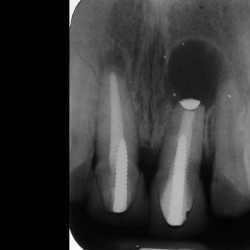

Inicio Especialidades Endodontia